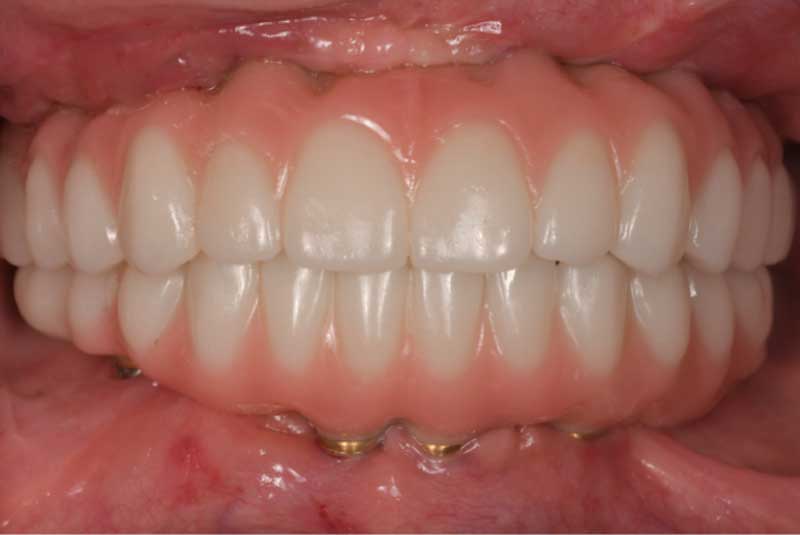

The patient had her implants placed 20 years ago. Four implants, particularly in the maxilla, were not positioned ideally for me to utilize and restore, while the four implants in the mandible were outdated and no longer functional. The patient's primary concern is to restore both function and aesthetics.

All on 6: Facial cut back (PFZ) Zirconia Full arch prosthesis for Maxilla and Mandible Before & After

All on 6 for both arches Implants (#3,4,6,11,13,14,18,21,22,27,28,31)